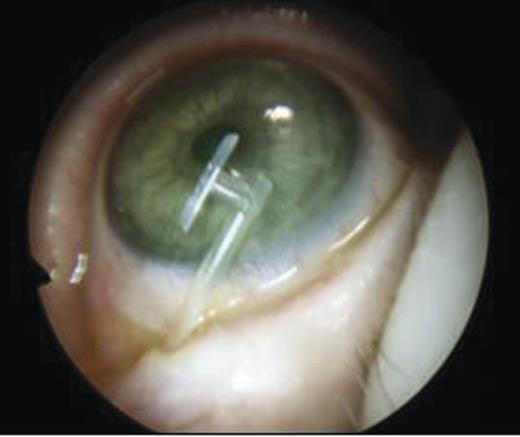

- An endoscopic left anterior ethmoidectomy was performed (Fig. 9) with marsupialisation of the mucocele (Fig. 9) and trimming of the DCR stent (Fig. 10)

Figure 9:Transnasal endoscopic left anterior ethmoidectomy and marsupialization of mucocele.

Figure 10:Post-operative view with trimmed DCR stent in situ in the left nasal cavity.

Post-operatively, she was discharged the next day and advised to administer chloramphenicol eyedrops as well as betnesol nasal drops for a week. The DCR stent remained in situ for 3 months and was removed in the clinic. There was clinical resolution of the medial canthal swelling and epiphora.